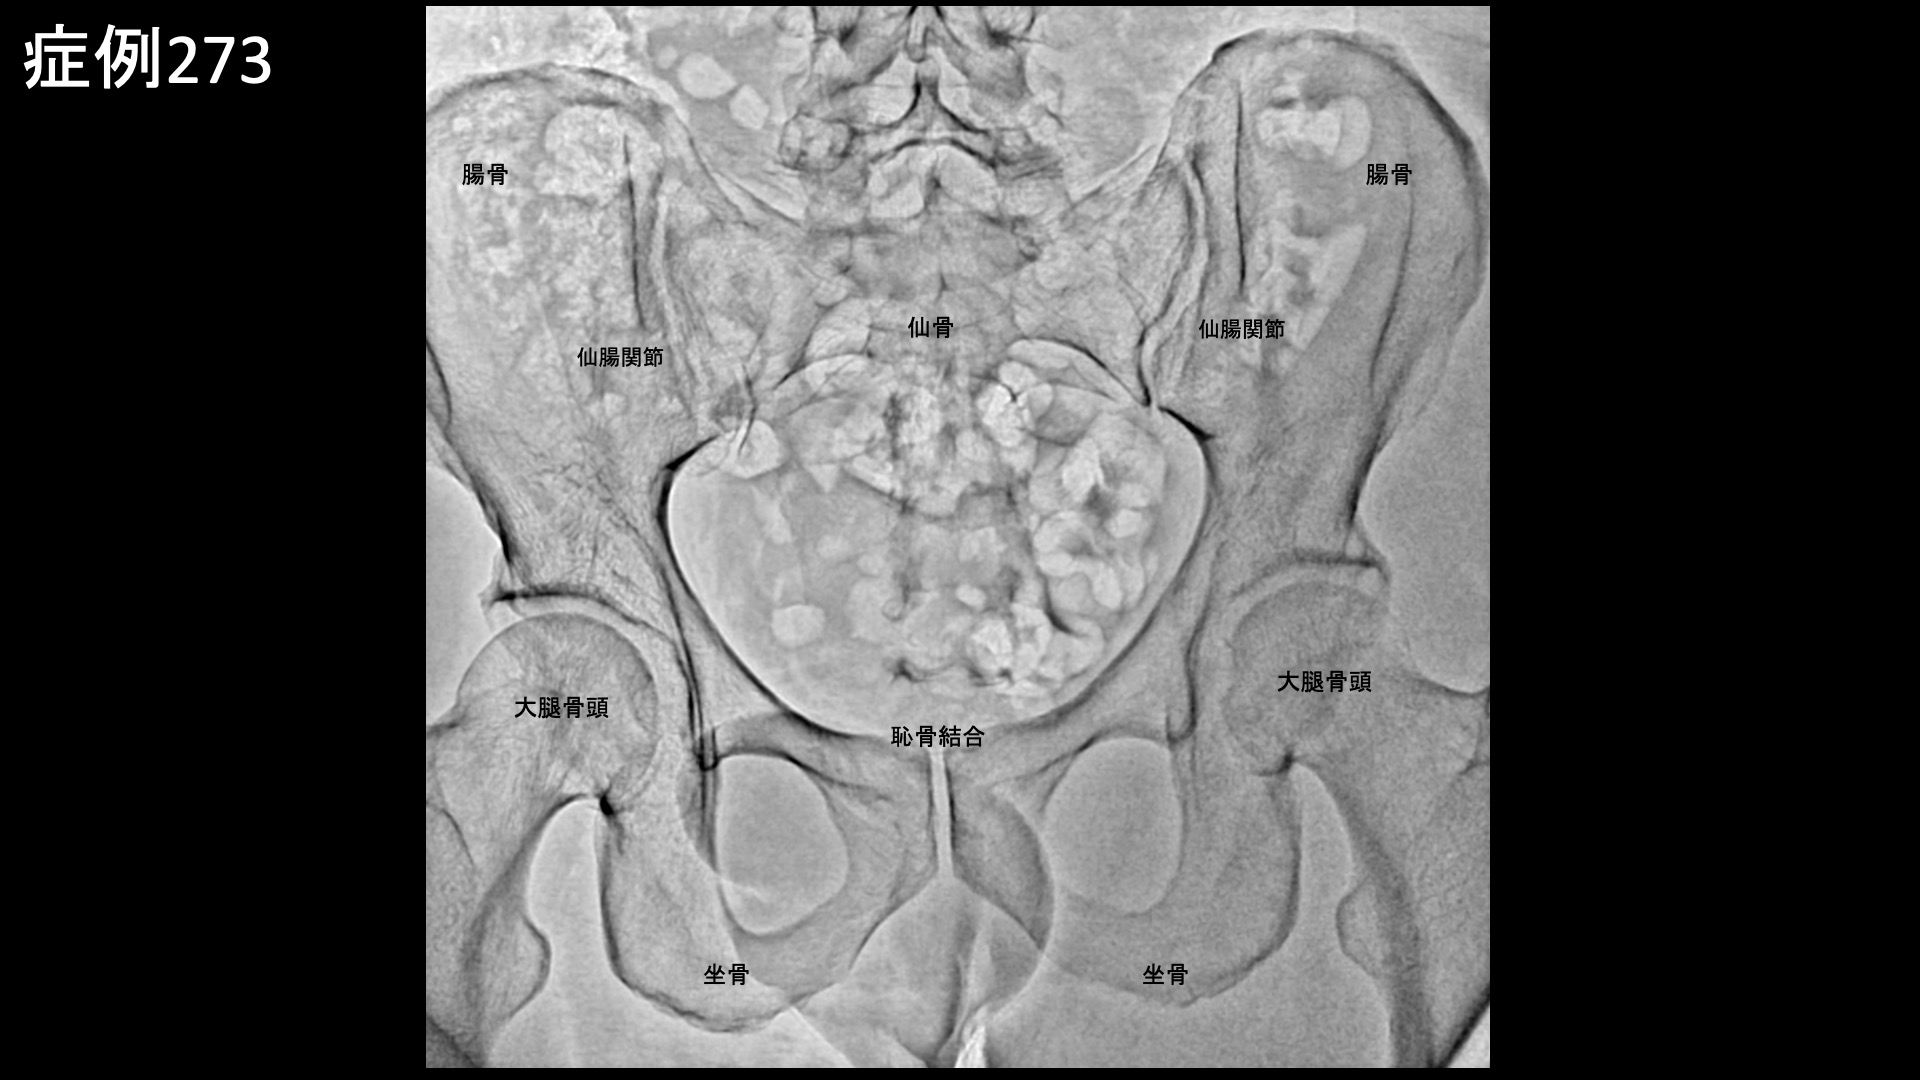

足:アキレス腱炎、足底筋膜炎、踵骨棘など 【30代:男性】マラソンランナーに生じた大腿裏付け根の痛み、ハムストリングス付着部炎に対するモヤモヤ血管治療(ハムストリングス付着部炎、仙腸関節障害) 2026.03.24 鴨井院長による動画解説 受診までの経過 マラソンにも参加するなどランニングを趣味としている方です。週に5-6回、14km/日程度走るのを日課としていましたが、9ヶ月前から右脚付け根の後ろ側、ハムストリングス付着部が痛むようになりました。その後も5ヶ月くらいはだましだましランニングを続けていましたが、症状が悪化してきたため走るのをやめて鍼灸治療に通いました。しかしながら、あまり改善がみられませんでした。その内に、ぎっくり腰を何回か起こし、腰痛も併発するようになりました。できればランニングは続けながら治したいという希望で、当院を受診されました。 診察時の所見 腰の動きを確認すると、前屈で中等度以上の制限があり、腰部や右ハムストリングス付着部に疼痛が誘発されました。後上腸骨棘近傍に圧痛を認めました。右ハムストリングス付着部において圧痛を認めたほか、負荷テストでも陽性でした。股関節は問題ありませんでした。レントゲンでは仙腸関節の骨硬化像や、開大傾向が認められました。ハムストリングス付着部である坐骨の骨表層不整像も認められました。その他の診察所見を含めて総合的に判断し、右ハムストリングス付着部炎および仙腸関節障害と診断しました。治療適応と判断し、モヤモヤ血管(病的新生血管)に対する運動器カテーテル治療(微細動脈塞栓術)を受けていただきました。 治療の所見 ハムストリングス付着部に重要な下殿動脈の分枝を治療した後、腰痛に対する腸腰動脈等を治療しました。ハムストリングス付着部炎においては、股関節周囲の血管も重要です。閉鎖動脈や内側大腿回旋動脈の血管造影では、モヤモヤ血管が濃染像として描出されました。治療後は画像上速やかに消失しました。それぞれで、再現痛も明瞭に確認されました。その他複数箇所の治療を行い終了しました。 *再現痛とは、薬液投与時に普段の痛みが一定程度再現される現象です。責任血管の同定のための参考とします。特に腰臀部領域ではモヤモヤ血管が描出されにくいため、再現痛の確認が重要です。 治療後の経過 治療翌日には炎症感がおさまり、2日後に再燃したように感じましたが、そこからどんどんと良くなってきました。治療後2週間、実は起床時の症状が最も悪かったのですが、それがだいぶ気にならなくなりました。痛みが良くなったためか、突っ張り感が気になりました。診察では、後上腸骨棘近傍の圧痛は消失していました。その翌日に、ハムストリングス付着部の違和感が消失しました。治療後3週間くらいで10kmほどランニングをしてみたところ、再び違和感が生じ、しばらく続きましたが、1週間くらいで気にならなくなりました。治療後1ヶ月半、前述内容の申告からランニング再開には時期尚早と判断し、1ヶ月ほど控えていただくこととしました。治療後2ヶ月半、日常生活ではほとんど痛みを感じることが無くなりました。徐々に運動を再開することとしました。走った後に炎症を感じたものの、元の状態からすると8-9割方改善しているということでした。治療後3ヶ月、16km/日のランニングを行うことができ、翌日に引きずるような症状もありませんでした。順調に改善していました。腰痛の訴えも無くなっていました。引き続き、慎重にフォローアップしていく予定です。 ハムストリングス付着部炎はモヤモヤ血管治療の適応疾患の一つであり、痛みは良く治まりますが、実際には同部位の組織損傷があるため、運動再開のリスクは個人差がかなり大きいです。重症になるほど、運動の再開は慎重にならなければなりません。特に、日常生活でも痛みが生じる内は負荷の大きなランニングは控える必要があります。痛みをこらえて、だましだまし走り続けると状況が悪化してしまいます。安静にするべき時は安静を守っていただき、しっかり治してからまた楽しんでいただきたいと思います。 ハムストリング付着部炎の詳細はこちら 【40代:女性】2年間悩まされた、交通事故後に絶えまなく続く首の痛み(むち打ち症;頸椎捻挫後遺症)に対するモヤモヤ血管治療(むち打ち症、頸椎捻挫後遺症、交通事故後遺症) 前の記事 【70代:女性】それほど目立たない発疹だったのにこんなに痛くなるなんて・・下腹部、脇腹に生じた発症1ヶ月半の帯状疱疹後神経痛 次の記事